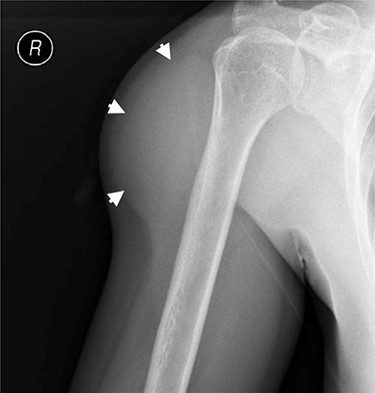

Externally rotated AP radiograph of the right shoulder and upper-arm. Short arrows indicate the tumoral mass.

To exclude calcifications, a shoulder radiograph was carried out. The radiograph confirmed a soft tissue mass located around the proximal humeral bone with an estimated size of 9 × 5 cm, without radiographically visible calcifications (Fig. 3). A normal bone structure without periosteal reaction or cortical invasion was reported.